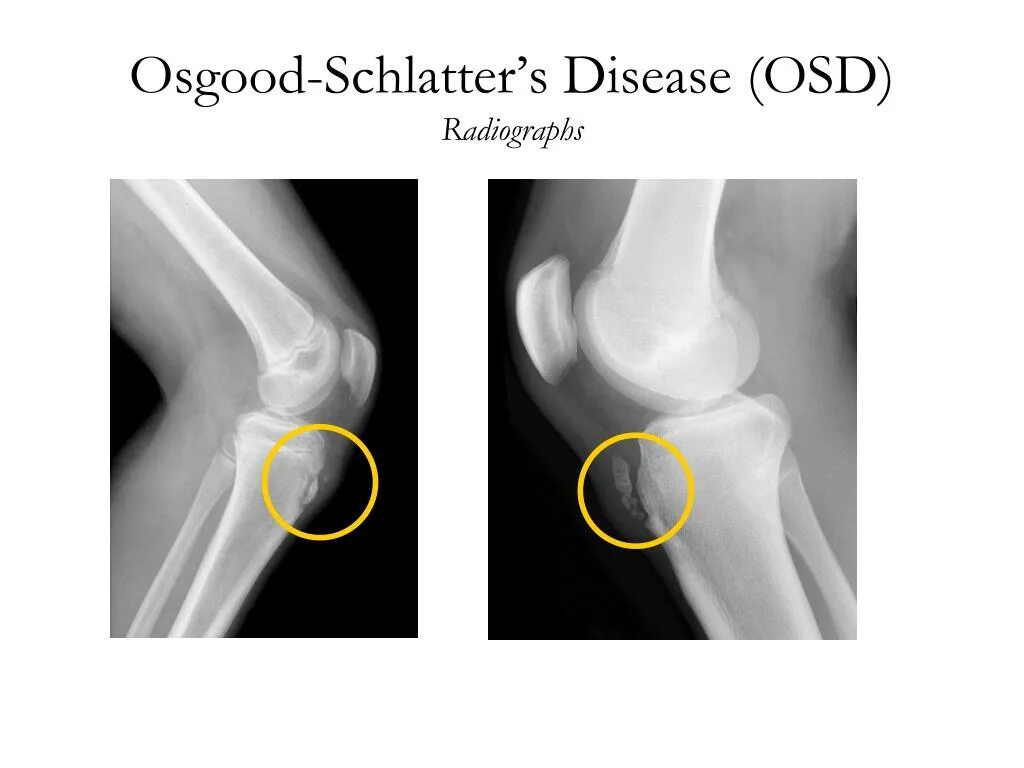

Болезнь осгут шляттера